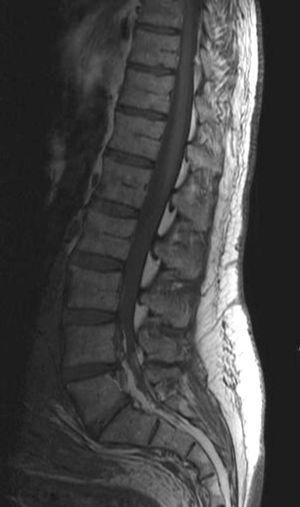

Se realizó una resonancia magnética (RM) de la columna lumbar (sin y tras contraste intravenoso) y se observaron, además de la masa retroperitoneal que comprimía la VCI, unas imágenes puntiformes y lineales hipointensas en todas las secuencias que ocupaban el espacio epidural adyacente al muro posterior de las vértebras lumbosacras, que se extendían a través de los agujeros de conjunción hacia las partes blandas perivertebrales (figs. 1-3). Esta alteración correspondía a estructuras vasculares dilatadas dependientes del plexo venoso epidural vertebral.

Fig. 2. Resonancia magnética ponderada en T2 (A) sagital línea media y (B) parasagital. En el espacio epidural anterior (A) y en los forámenes de conjunción (B) se aprecian estructuras vasculares con aspecto serpinginoso y arrosariado (flechas).